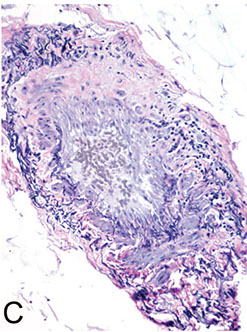

Glomus tumor

B9, wide age range, comes from modified sm muscle of glomus body (specialized AV anastamosis dealing c thermoregulation)

- usually under fingernails (normal glomus cells are modified sm muscle cells and are normally found on sides of digits and coccyx

Micro: branching vascular channels separated by stroma c glomus cells that are small, regular, round c no nucleoli seen in nests / aggregates ("string of black pearls"); glomus cells found around vessels (vessels can be HPC-like)

C, Glomus tumor shows small, uniform cells